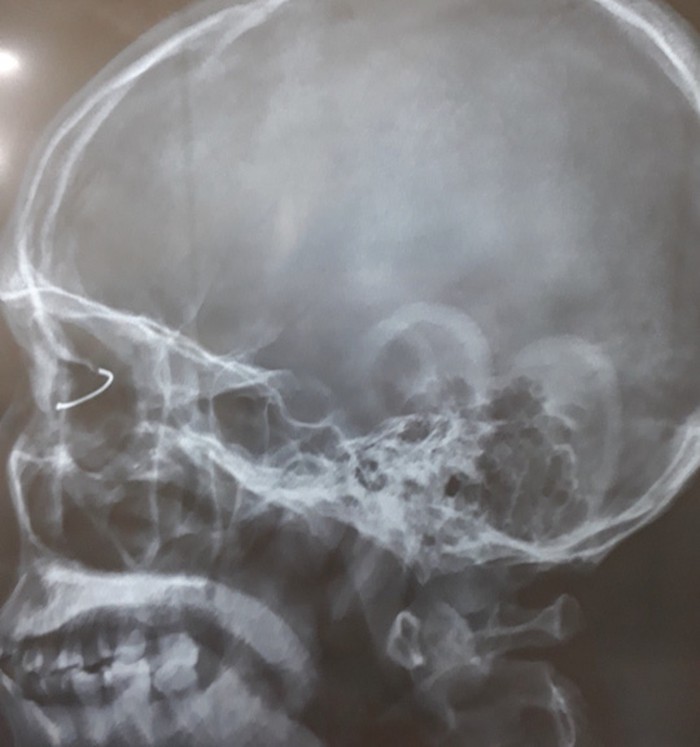

Trên hình ảnh phim X - quang các bác sĩ thấy một chiếc đinh cong, tiên lượng chưa xuyên thấu nhãn cầu nhưng dị vật này đã đâm xuyên giác mạc, qua mống mắc, xuyên qua thủy tinh thể làm đục vỡ thủy tinh thể.

Phim X-quang cho thấy vị trí chiếc đinh cắm sâu trong nhãn cầu bệnh nhân - Ảnh: VNexpress. |